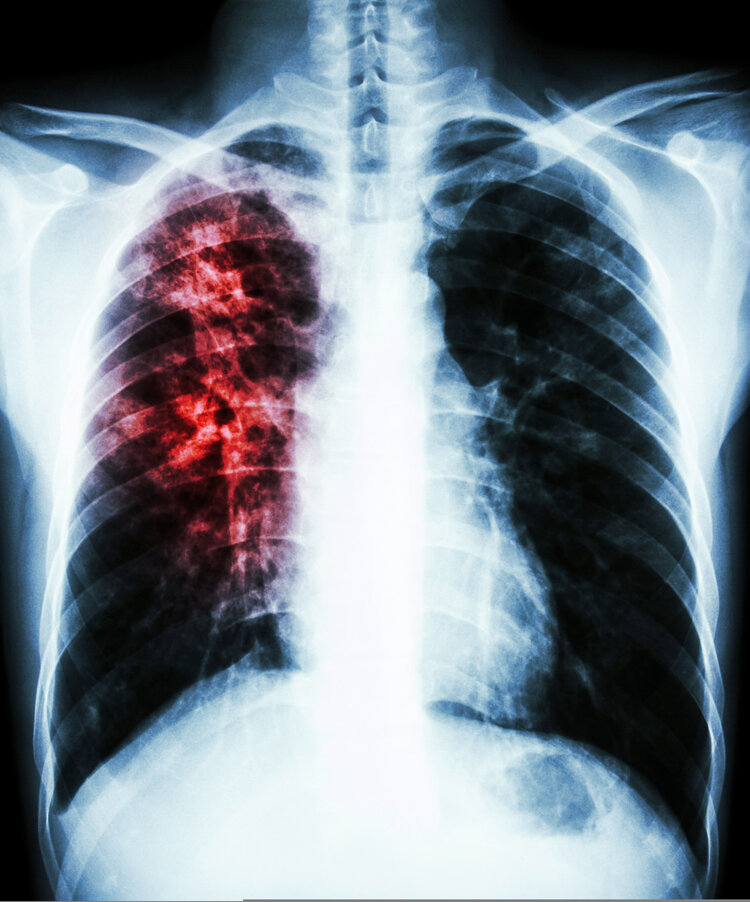

文章图片

肺癌:当然了 , 肺部出现阴影也可能是肺癌所致 。 肺癌患者在临床上的检查会出现球形阴影 , 边缘非常模糊 , 会出现“毛刺”状的边缘 , 部分患者还会出现片状形态 。

罹患肺癌的患者多会伴随应激性咳嗽、声音嘶哑、发热以及消瘦等症状 。